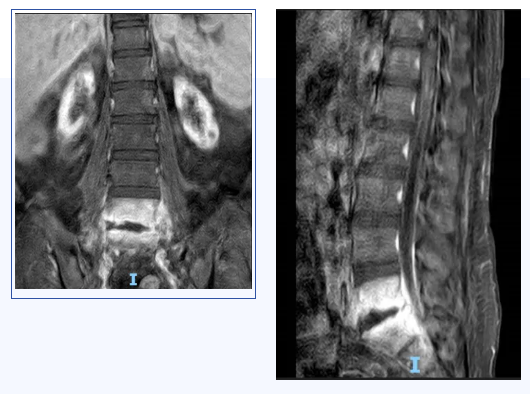

脊柱微创外科在粤西拥有最专业的脊柱感染、脊柱创伤、脊柱退变、脊柱肿瘤及脊柱畸形诊疗团队。患者既往有“慢性肾衰竭(尿毒症期)、甲状旁腺功能亢进、高血压病3级(极高危)、贫血”等疾病,面对复杂的病情,魏波主任和胡资兵教授在患者入院后迅速为其完善检查。抽血结果显示感染指标明显升高,腰椎CT、增强MRI显示腰5、骶1椎体、椎旁及左侧背部软组织异常信号并明显增强,考虑感染性病变。胡资兵教授团队迅速诊断患者为“化脓性脊柱炎”,并积极为患者施行手术治疗做准备。

患者感染病灶位于腰5、骶1,骶1骨质破坏,置入椎弓根钉强度欠佳,容易松动、拔钉,导致内固定失败。传统使用髂骨螺钉替代骶1椎弓根钉,但髂骨螺钉存在钉尾突兀刺激皮肤、与近端腰椎椎弓根钉不在同一纵线、连接困难等缺点。鉴于脊柱微创外科团队过去已在美敦力S7系统辅助下成功完成多例精准导航脊柱外科手术,胡资兵教授团队在征得患者及家属同意后,决定采用“C臂导航下经后路腰5、骶1感染病灶清除、椎管减压、S2AI螺钉、腰椎椎弓根钉棒内固定术”来解决此难题。